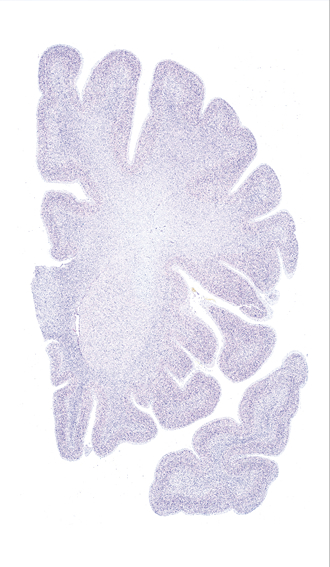

Frontal sections (Nissl) from the Atlas Brain: Gallery Slice Single

Microscopy

-16,6 mm

Slice ID: r2-0470

Plate NR: 11

Position: -16,6 mm